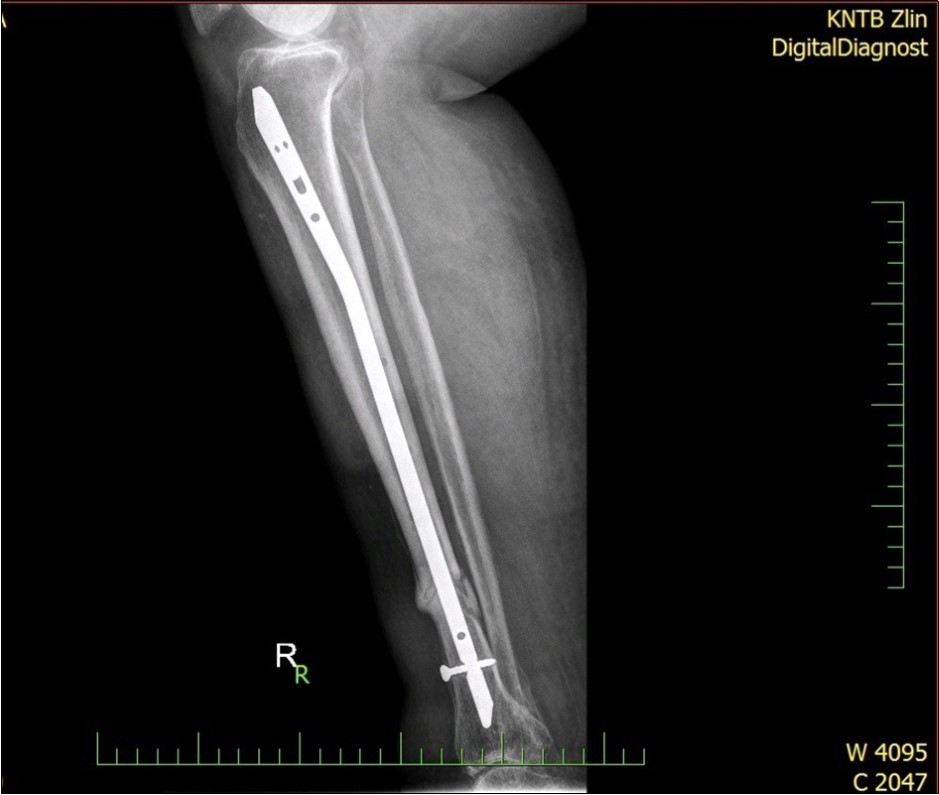

Figure 33. X-ray documentation of the whole treatment of tibia fracture. External fixation was used throughout the treatment until bone was healed. From 9.October 2015 to 2.February 2017